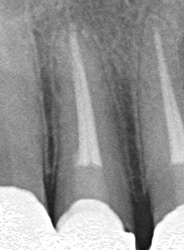

おできは治らない

治療前

治療後

| 主訴 | 右下が腫れて痛かったので受診したが、切開して膿を出して抗生剤をのんだら落ち着いたが、その後おできが出来た。これは治らないと言われた。 |

|---|---|

| 施術内容 | 保存治療と外科的根管治療の併用 |

| 治療期間 | 3ヵ月 |

| リスク・副作用 | 外科的侵襲 |

| 費用 | 保存治療:165,000円 外科手術:165,000円 骨再生医療:165,000円 相談料:44,000円 |